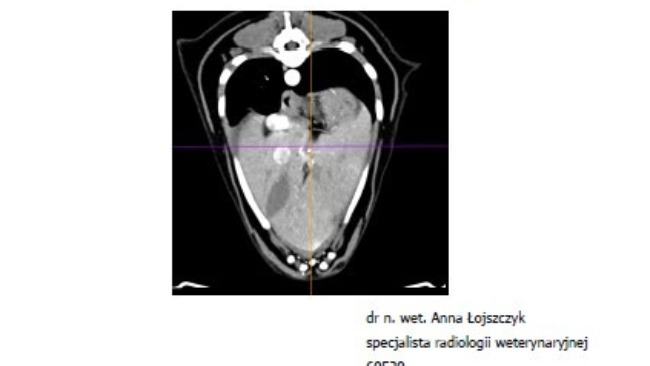

Atenka jest już po tomografii, po biopsjach śledziony i węzłów chłonnych, oraz po punkcji płynu z jamy opłucnej. Pozostaje nam teraz długie wyczekanie na opisy i na wyniki badań.

Badania moczu, badanie krwi, USG jamy brzusznej, echo serca, rtg, wizyta onkologiczna.... To wszystko co już mamy za sobą i nadal nie wiadomo co się z Atenką dzieje i nie wiadomo jak ją leczyć. Wykluczony został zespół Cushinga. Wykluczone zostały choroby serca. Podejrzenie chłoniaka na razie nie zostało potwierdzone. Diagnostyka trwa dalej, a koszty rosną w przerażającym tempie. Przed nami tomografia oraz biopsja śledziony, biopsje węzłów chłonnych, badanie cytologiczne płynu z jamy opłucnej. To koszt minimum 3000 zł.